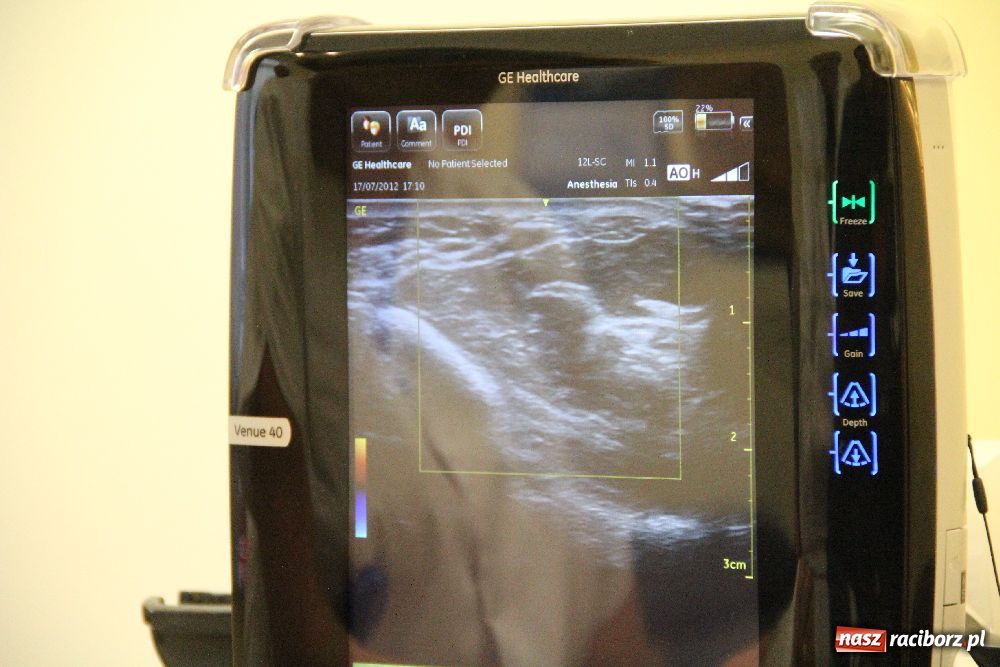

Szpital Rejonowy im. dra Józefa Rostka wzbogacił się o najnowocześniejszy aparat ultrasonograficzny w Polsce. - To pierwszy tego typu aparat w naszym kraju. Jego zastosowanie w diagnostyce i leczeniu zwiększa bezpieczeństwo pacjenta - powiedział Włodzimierz Kącik, dyrektor ds. medycznych.

Oddział anestezjologii i intensywnej terapii raciborskiego Szpitala Rejonowego ma na wyposażeniu nowoczesny aparat ultrasonograficzny. - Nowy aparat daje ogromne możliwości, ma szerokie zastosowanie zarówno w diagnostyce jak i leczeniu pacjenta - powiedział Włodzimierz Kącik, dyrektor ds. medycznych raciborskiej lecznicy. - Jest to dla nas bardzo przydatne urządzenie, wysokiej jakości. Dzięki zastosowaniu tego typu ultrasonografu można np. bardzo precyzyjnie podać środek znieczulający w mniejszej ilości, a przecież środki znieczulające nie są obojętne dla organizmu chorego, dlatego też podanie ich w mniejszej dawce jest niezwykle istotne - powiedziała Małgorzata Składanowska, ordynator oddziału anestezjologii i intensywnej terapii Szpitala Rejonowego w Raciborzu.

- Personel jest bardzo zadowolony z nowego sprzętu. Jest to mały, mobilny aparat, który dodatkowo można doposażyć w różnego typu głowice, dzięki czemu będzie można wykorzystać ten sprzęt na chirurgii czy internie. Póki co ultrasonograf był profilowany pod kątem anestezjologii - powiedział dyrektor Kącik. - Nowy ultrasonograf wygląda niepozornie, ale jak widać, ma duże możliwości - zauważył dyrektor szpitala Ryszard Rudnik.

Warto podkreślić, że zakup sprzętu był dofinansowany w 50% przez Stowarzyszenie Narodowy Fundusz Ochrony Zdrowia. - Zdecydowaliśmy się dofinansować zakup ultrasonografu ze względu na to, że wspieramy tych, którzy sami chcą sobie pomóc, którzy dają coś od siebie. Racibórz zwrócił się do nas z prośbą, pozytywnie rozpatrzyliśmy ten wniosek i sfinansowaliśmy zakup aparatu ultrasonograficznego w połowie, drugą połowę dołożył szpital. Cena aparatu wyniosła 77 tysięcy złotych - powiedziała Teresa Przygoda, dyrektor Stowarzyszenia NFOZ.